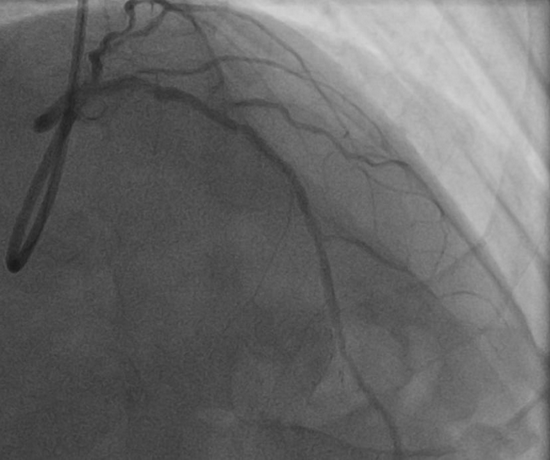

冠脉造影提示左前降支近端急性闭塞